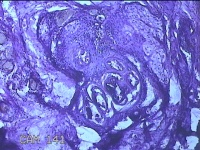

面部肿物

性别

男

年龄

30岁

临床诊断

皮赘;皮肤感染;脚癣

一般病史

面部起疹3月,不痒。

标本名称

大体所见

灰白暗红色肿物0.8x0.5x0.2cm一个,表面糜烂。